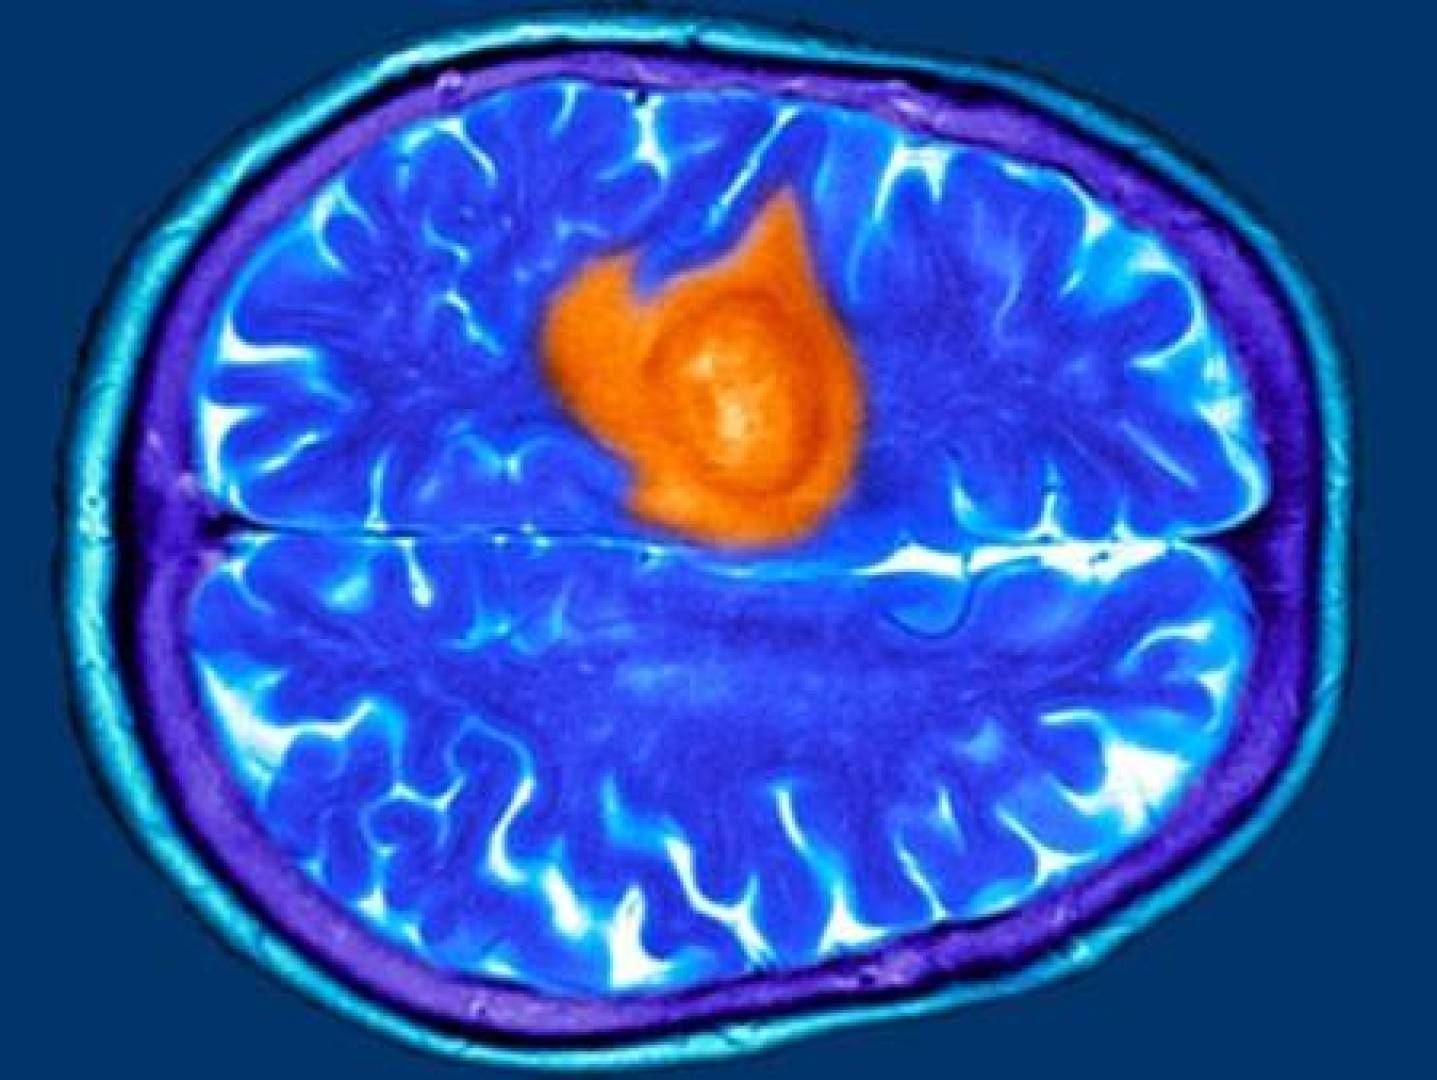

توصل فريق دولي من الباحثين إلى طريقة جديدة للكشف عن العلامات البيولوجية المبكرة لمرض الزهايمر قبل ظهور أي أعراض سريرية.

وتمثل هذه الدراسة نقلة نوعية في مجال التشخيص المبكر، إذ يمكن مراقبة تراكم بروتين مرتبط بالالتهاب العصبي في مناطق محددة من الدماغ، بالتزامن مع ظهور أولى المؤشرات المرضية.

ظهرت أول لويحات أميلويدية في عمر 1.5 شهر في منطقة السوبكولوم المرتبطة بالذاكرة والحصين (Hippocampus).

في نفس الوقت، لوحظ ارتفاع مستوى بروتين TSPO، وهو مؤشر على الالتهاب العصبي.

أظهرت التحليلات أن ارتفاع TSPO مرتبط بنشاط الميكروغليا، وهي خلايا مناعية في الدماغ تتجمع حول اللويحات الأميلويدية.

هذا يشير إلى أن TSPO لا يعكس الالتهاب العام، بل يحدد التفاعل المحدد بين الميكروغليا والبنية الأميلويدية المسببة للمرض.